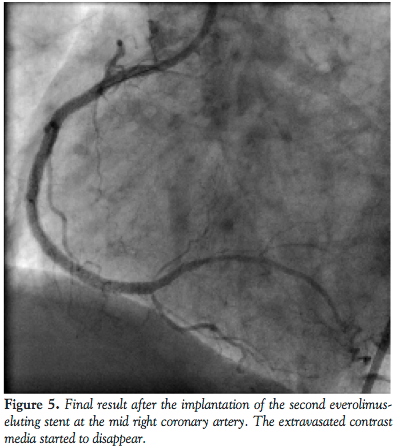

reasonable to assume that the perforation occurred near the distal stent edge as a consequence of the high-pressure predilatation. To seal the perforation, the above-mentioned net wrapped stent, a 2.5 mm x 15 mm MGuard was introduced in the territory of crux cordis. The stent was positioned to cover the distal edge of the previously implanted Endeavor stent and the perforated posterolateral branch as well, and then it was deployed at nominal pressure (Figure 3). The overlapping part of the stent was postdilated with the aid of the stent balloon at 17 atm. The implantation of the MGuard stent resulted in successful sealing of the perforation and the contrast agent extravasation was abolished. The original restenotic lesion and the de novo mid segment lesion were managed by deploying 2 Xience Prime LL 3 mm x 33 mm stents (Abbott Vascular) at 20 atm (Figures 4 and 5). No signs of hemodynamic instability appeared. After the intervention, echocardiogram revealed only 6-7 mm pericardial fluid localized at the left ventricular posterior wall. There were no significant ECG changes and the maximum CPK level was 260 U/L (upper limit of normal is 170 U/l). The patient remained stable during the following hospital stay. She was discharged on a daily dose of aspirin 300 mg and clopidogrel 150 mg. At 6-month follow-up neither angina pectoris, nor sign of coronary ischemia were revealed.